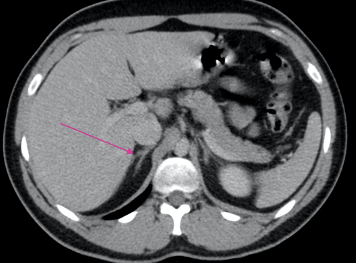

What is indicated by the arrow?

Lateral limb of adrenal gland

Medial limb of adrenal gland